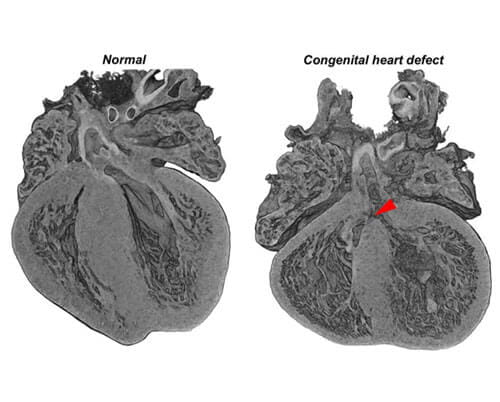

Congenital heart defects are the most common birth defect and affect approximately 1% of births per year in the United States. We aim to identify novel gene mutations linked to these defects and understand their impact on heart development.

Dr. Mead is a trained developmental and molecular biologist with a keen focus on cardiovascular development and disease. His research centers on how changes in the extracellular matrix results in dysfunctional heart development and resulting congenital heart defects. Dr. Mead utilizes mouse models of congenital heart disease, biochemistry and proteomics to understand the molecular mechanisms underlying these diseases towards the development of therapeutic approaches. His current research focus is on the novel concept of inhibiting a protease that remodels fibrillin microfibrils in the aorta in an effort to identify a therapeutic for Marfan syndrome.

Impact of Our Research

The short-term impact of our research is identifying and understanding the molecular mechanisms of heart development and disease. Congenital heart defects are the most common birth defect and affect approximately 1% of births per year in the United States. We aim to identify novel gene mutations linked to these defects and understand their impact on heart development. Identifying these gene mutations will allow for early detection and, hopefully, early intervention. The long-term impact of our research is to uncover the molecular mechanisms of these disease-causing gene mutations to identify new ways to treat congenital heart defect patients.